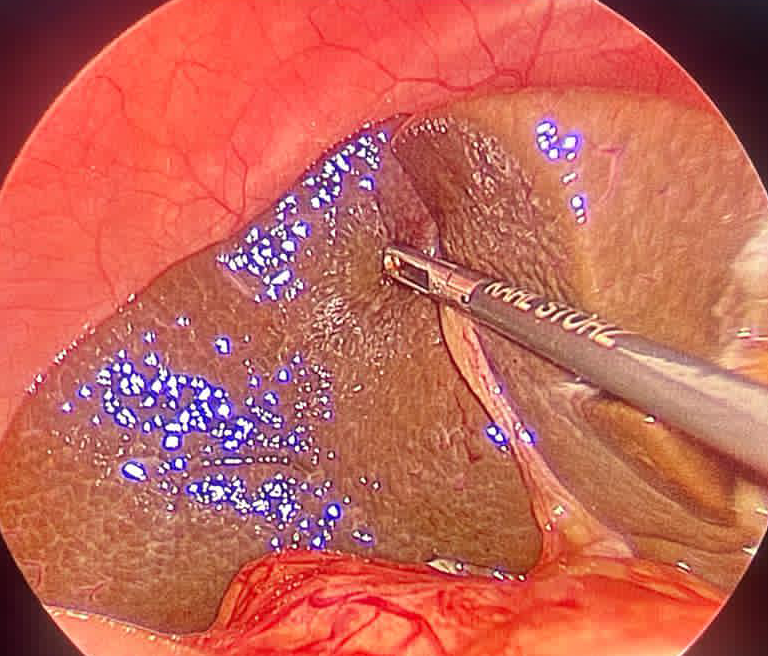

Fetal Interventions

Reaching inside the uterus to assist a troubled foetus is known as foetal intervention. Over the past few decades,